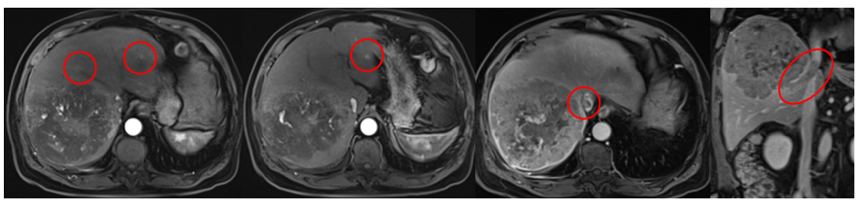

2020年4月20日上腹部MR示,原发性肝癌伴肝内及肝静脉浸润(图1)。中国肝癌(CNLC)分期Ⅲa期。

图1.2020年4月20日上腹部MR

患者男,61岁,乙型肝炎病史20余年。2020年8月初超声肝占位,MRI考虑HCC伴门静脉右前支癌栓。2020年8月19日外院行肝癌根治术,术后病理:肝细胞癌,粗梁型,结节性肝硬化。2020年9月17日外院行TACE。2020年11月20日我院MR:肝癌术后肝内多发转移(图1)。2022年11月25日AFP为354.6ng/ml。

图1.2020年11月20日MR